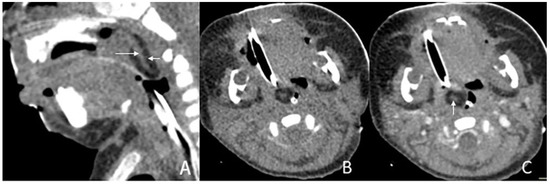

Figure 2. CT of a 1-month and 16-day girl presenting with throat congestion 29 days after birth. (A,B) Sagittal and axial CT, displayed in the soft-tissue window, shows a sausage-like fat density mass (short arrow) with a soft tissue density core (long arrow) originating from the left lateral pharyngeal wall. (C) Axial, postcontrast CT, displayed in the soft-tissue window, shows that the lesion’s stalk is slightly enhanced (arrow), but the rest of the lesion is not enhanced.

The size of masses varied from 0.6 to 4.3 cm. There were 11 (78.6%) cases with the largest diameter of the mass greater than 2 cm. The shapes of the masses were varied. Eleven (78.6%) cases presented with typical pedicled masses containing fat and a central core of soft tissue, including sausage-like masses in five (35.7%) cases, tongue-like masses in four (28.6%) cases, and pear-like masses in two (14.3%) cases. Of the eight patients who underwent MRI scans, there were five (62.5%) patients whose masses had high signal intensity on T1-weighted and T2-weighted sequences with a low-signal central core whose signal intensities were similar to those of muscles. The high signal intensities on all sequences were similar to the fat signals and attenuated by fat suppression. The central core demonstrated mild enhancement following intravenous gadolinium administration, while the surrounding components of the fat signals demonstrated no enhancement in one case (Figure 1). There was no reduced diffusion of the five patients who underwent DWI. Via CT, there were 10 (83.3%) cases whose masses appeared as well-circumscribed fat attenuation masses surrounding a central core of soft tissue. The central core was mildly enhanced following intravenous iodixanol administration, but the fat components were not enhanced in one case (Figure 2). There were five patients who received both MRI and CT.

Upon MRI, most of the masses were found to have heterogeneous high signal intensity on T1-weighted and T2-weighted sequences with a low-signal central core whose signal intensities were similar to those of muscles. The high signal intensities on all sequences were similar to the fat signals and attenuated by fat suppression. The central core demonstrated mild enhancement following intravenous gadolinium administration, while the surrounding components of the fat signals demonstrated no enhancement. The central core helps us trace the origin of the mass, which is important for the choice of surgical method. Characteristic imaging features on CT include well-circumscribed masses containing fat and linear soft tissue–density components centrally that correspond to the fibrovascular stalk [2]. The central core was mildly enhanced, as expected for fibrous tissue, but the fat components were not [23]. These findings corresponded well with the MRI and CT features previously described [24,25]. Intracranial or intraspinal extension was not found in any of the lesions in the present study, which was consistent with existing reports.